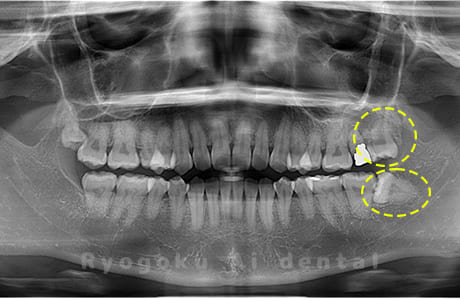

Case04

-

- 原因

- 上顎の親知らず、下顎の水平埋伏の親知らず

- 治療内容

- 上顎の親知らず、下顎の水平埋伏の親知らずを抜歯したケースです。

<リスク・副作用>

手術後は痛み、腫れ、痺れなどの副作用が生じる場合があります。